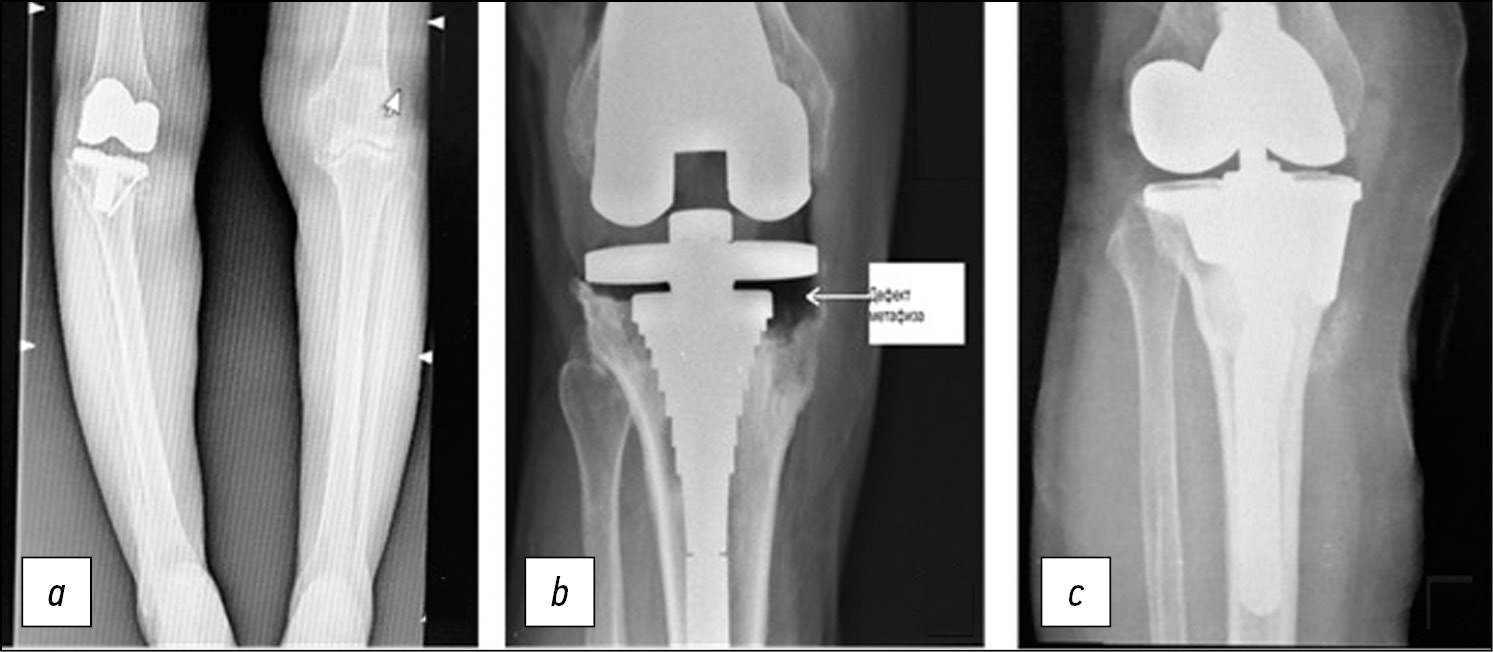

При оказании помощи пациенту Ч., возраст 62 года, поступившему на 2-й этап лечения перипротезной инфекции в НИИ травматологии, ортопедии и нейрохирургии (НИИТОН, Саратов), на рентгенографии был обнаружен неправильно сросшийся перелом бедренной кости, что создавало потенциальные сложности для установки интрамедуллярного стержня (рис. 2).

Рис. 2. Рентгенограммы больного Ч., 62 года. Дефект типа F1/T2B по AORI (a, b). Результат установки ревизионной системы с метафизарными втулками (c, d).

Fig. 2. X-ray images of the 62 y.o. patient Ch. with F1/T2B AORI defect (a, b). The outcome of implanting a revision system with a metaphyseal sleeves (c, d).

Согласно предложенному алгоритму, было принято решение использовать метафизарную втулку. При обработке метафизарной части кости выявили дефект типа F1/ T2В (ограниченный центральный дефект) по AORI, в связи с чем приняли решение использовать метафизарный фиксатор типа втулки DePuy; при обработке рашпилями удавалось получить адекватную ротационную и аксиальную стабильность импланта. Согласно разработанному алгоритму, использовали ревизионную систему с метафизарными втулками, что обеспечило хорошую первичную стабильность и соблюдение принципа зональной фиксации ревизионного эндопротеза коленного сустава.